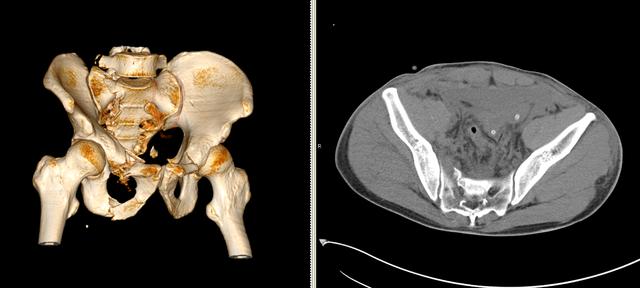

15分鐘后筆者在ICU看到了患者。該患者騎摩托車時發(fā)生交通事故后摔倒,腰骶部著地,當即感骨盆部及腰背部劇烈疼痛,為持續(xù)性劇烈脹痛,會陰部及右下肢麻木不適,不能站立及行走。被緊急送到解放軍第306醫(yī)院急診時已處于失血性休克失代償期,患者經(jīng)抗休克治療后生命體征逐漸平穩(wěn),急診以“失血性休克,骨盆骨折,尿道損傷,膀胱造瘺術(shù)后”收住ICU。

次日午間患者無明顯誘因出現(xiàn)大出血,血色素下降到60g/L。ICU、泌尿外科、骨科等專家緊急會診,一致決定立即行介入止血手術(shù)。